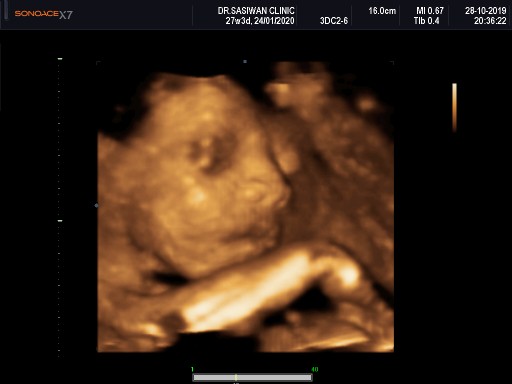

บ้านนี้ตอน 27 วีคค่ะ แต่รวมในแพ็คเก็ตคลอด

27w คลินิคที่ฝากครรภ์ชลบุรี 1,800฿ค่ะ